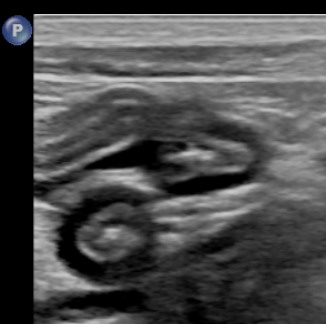

feline IBD(inflammatory bowel disease) cast ultrasonographic image sample

Well-demarcated thickening of the muscular layer with relatively preserved stratified wall structure.